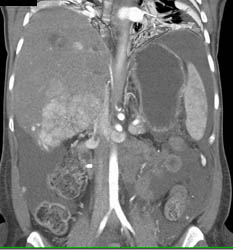

Hepatoma in Cirrhotic Liver